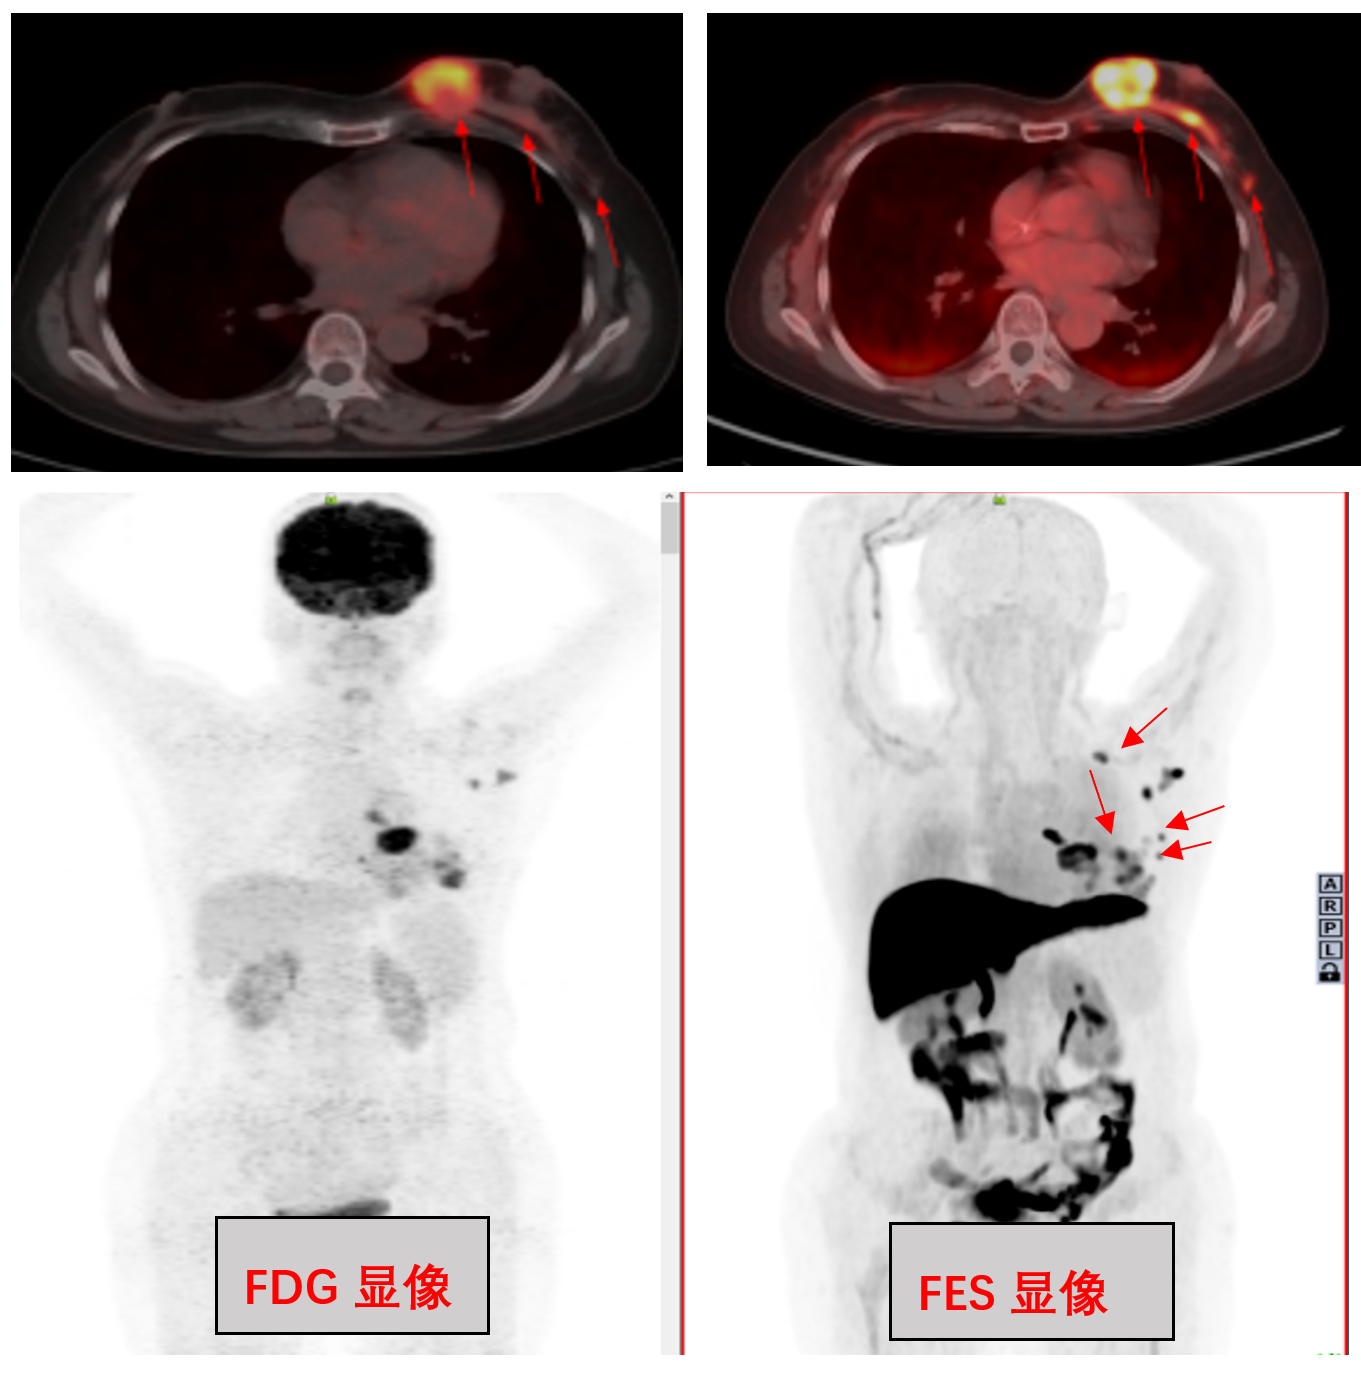

11.png患者,女,60岁。发现左乳肿物1周。活检病理结果:伴粘液分泌的浸润性导管癌II级,局部伴微乳头状分化。附免疫组化结果:ER+++90%,PR+++80%,HER-2(1+),AR+15%。5月6日和5月15日分别行FDG PET/CT检查和¹⁸F-FES PET/CT。结果显示:患者左乳肿瘤呈高代谢病灶,FES摄取较FDG摄取显著增加,腋下及锁骨上区FES显像发现更多转移淋巴结(红色箭头)。

据色情导航 核医学科主任吴巍介绍,¹⁸F-FES是雌二醇 (16α-¹⁸F-17β-fluoroestradiol)的缩写,是目前临床应用最为广泛的雌激素受体 (estrogen receptor,ER) 显像剂。¹⁸F-FES PET/CT显像适合于ER高表达的乳腺癌患者,通过PET/CT显像可以一次性、全面、无创地对全身多处病灶进行定性及半定量分析 ER 表达状况,特别是在难以活检的部位具有明显优势;对ER阳性病变的识别具有较高的特异性,在检测疑似病变、转移灶方面显示出较高的灵敏度。通过¹⁸F-FDG 和¹⁸F-FES双靶联合显像,发现糖代谢阴性的隐匿转移灶,提高转移灶检出率。当¹⁸F-FDG和¹⁸F-FES摄取同时增加时,¹⁸F-FES有助于鉴别ER阳性的转移灶。¹⁸F-FES能够检测到内分泌治疗期不同病灶的ER变化,发现内分泌治疗对不同病灶内受体作用的差异,对ER阳性乳腺癌患者内分泌治疗有重要指导意义;对于治疗无效的患者,可以及时发现并及时更改治疗方案。同时,他还强调了¹⁸F - FDG 和¹⁸F- FES 双靶显像的适应症,包括:病理学诊断的ER阳性乳腺癌患者;ER阳性乳腺癌患者术前评估、治疗前分期及治疗决策选择;ER阳性乳腺癌患者治疗中期疗效判定;ER阳性乳腺癌患者治疗后期随访、复发及转移检测;ER阳性乳腺癌患者治疗后出现疑似转移病灶,判断病灶性质;指导病理学活检部位选择,明确活性靶区位置;指导病灶放疗靶区精准勾画等。